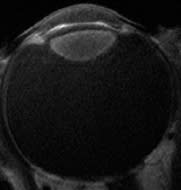

Currently, the Visian ICL (Staar Surgical, Figure 3) is the only alternative viable refractive procedure to LASIK that helps to maintain superior outcomes. This phakic posterior chamber lens is inserted through a 2.5mm self-sealing corneal incision and has safely expanded our refractive surgical candidates' options. The lens can be fitted for a patient who has a refractive error as low as −3.00D; however, the best benefit is observed in patients who are outside of the safe parameters of LASIK—those with corneas that are too thin, topographies that are questionable or demonstrate irregularities, and patients who have exceptionally high myopic refractive errors.

Figure 3. The Visian ICL is an alternative for poor LASIK candidates.